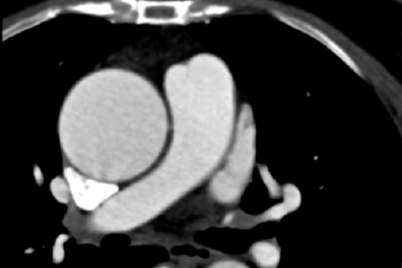

常州二院成功完成全国首批 EV-ICD 植入手术

2026-03-18

53 岁患者遇心脏复杂难题,南医大三附院成功为其实施主动脉瓣成形联合升主动脉置换术